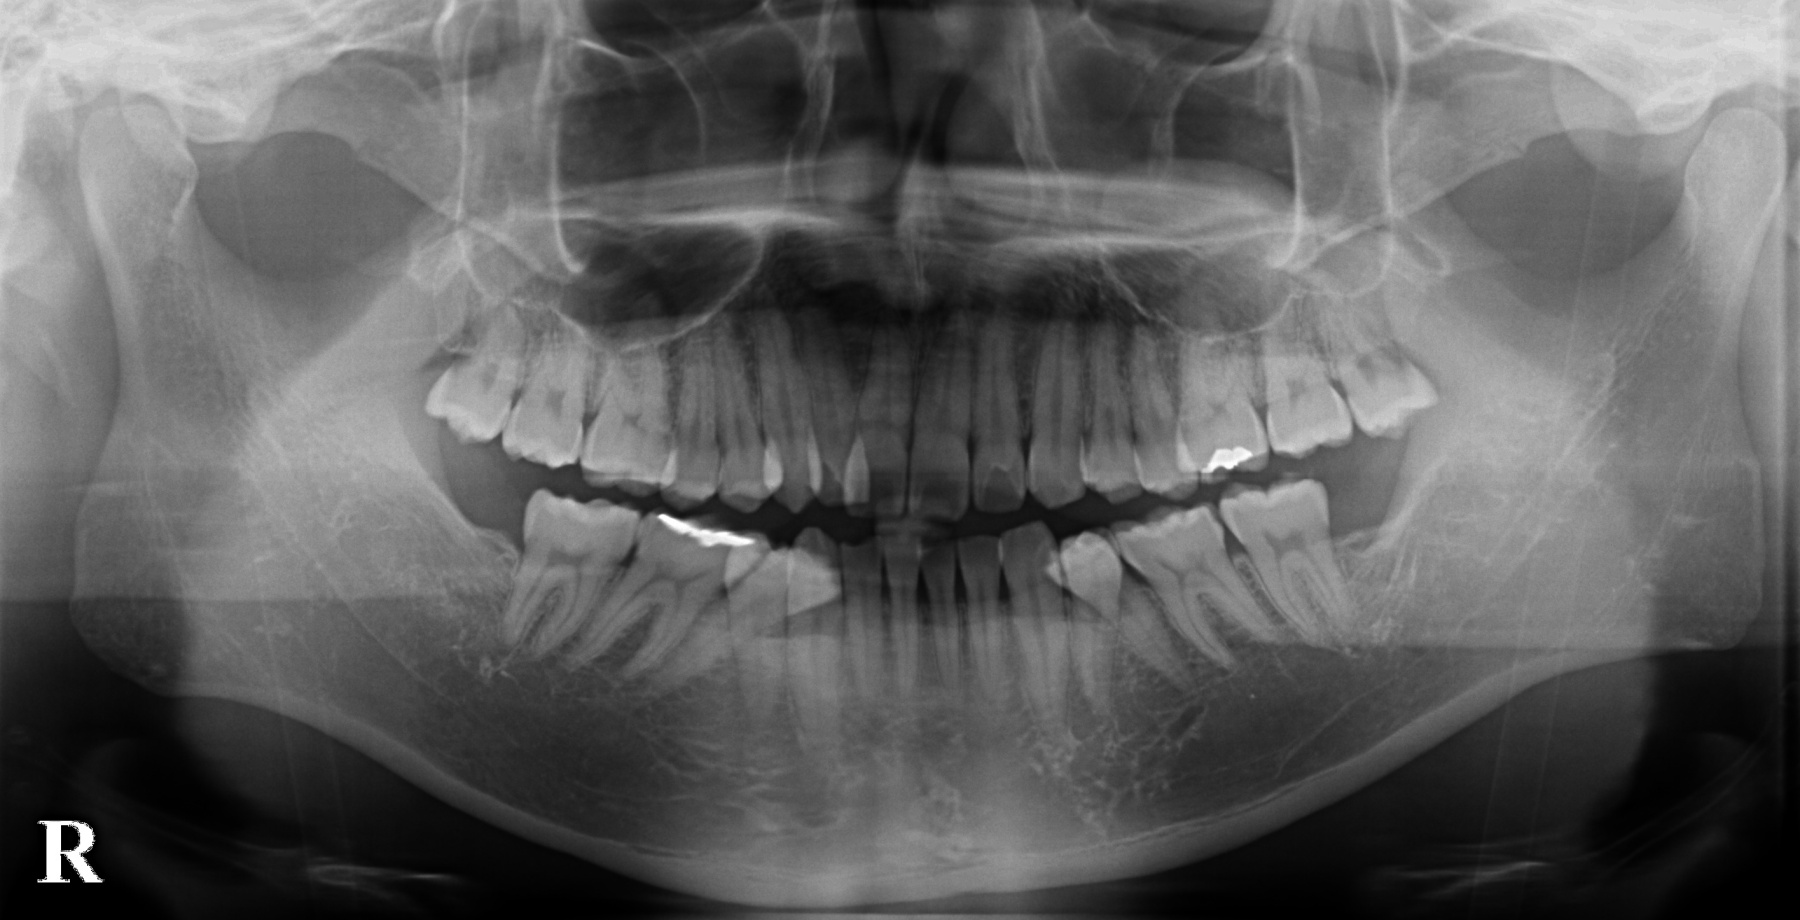

当医院では歯茎の検査やお口全体のレントゲン写真を用い、歯周病の有無を確認いたします。

歯の根の先にうみが貯まり、レントゲンに黒く映っています。